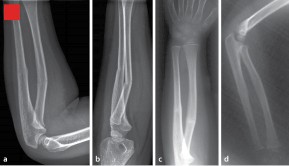

• Unterarmschaft Springerlink

Unterarmschaft Springerlink Reinhold Naegele